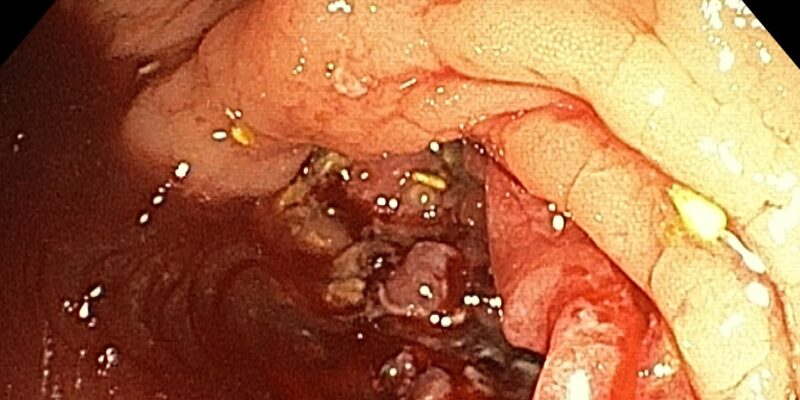

Caracterizarea endoscopică prin lumină albă poate ridica suspiciunea de polip malign cu evoluție către cancer colorectal prin aprecierea morfologiei, dimensiunii, localizării și modificării morfologice maligne brute cu aspect infiltrativ, vegetant. Ca metode auxiliare precum Narrow Band Imaging sunt aplicate tehnicile...

Colonoscopia completată de prelevarea de biopsii este explorarea care stabilește diagnosticul de certitudine în cazul unei formațiuni tumorale localizate la nivelul colonului și rectului . În momentul în care, în timpul colonoscopiei, este decelată o formațiune tumorală ce nu poate...